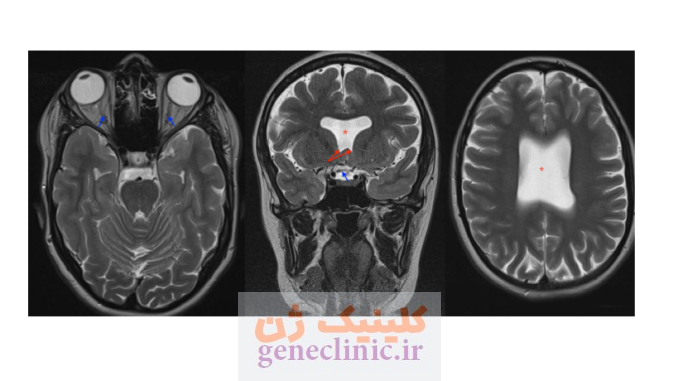

سپتوم پلوسیدوم (septum pellucidum) یک صفحه نازک از بافت عصبی است که دو نیمکره چپ و راست مغز را از هم جدا میکند. در برخی موارد این ساختار وجود ندارد یا به طور کامل تشکیل نشده است. این ناهنجاری در برخی موارد در همراهی با عدم تکامل عصب بینایی (Optic Nerve Hypoplasia) و اختلال عملکرد غده هیپوفیز (Pituitary Gland Dysfunction) دیده می شود که به این وضعیت دیسپلازی سپتو-اپتیک گفته می شود.

- در دیسپلازی سپتو-اپتیک ، علاوه بر عدم وجود سپتوم پلوسیدوم، هیپوپلازی اعصاب بینایی و / یا ناهنجاری های هیپوتالاموس-هیپوفیز وجود دارد.

- MRI مغز جنین برای ارزیابی اعصاب بینایی و chiasm ی بینایی, غده هیپوتالاموس-هیپوفیز و بررسی ناهنجاری های احتمالی در قشر مغز.